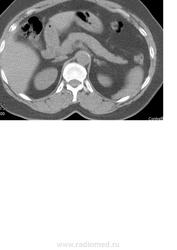

Добрый день! помогите пожалуста описать исследование. Пациентка 51 г.р., по УЗИ гипоэхогенное образование в левой доли печени 3х3,5 см с четким, неровным контуром.

Кистозное образование(?) размерами.., плотностью.. едН, расположено там то. Я думаю, что это киста.